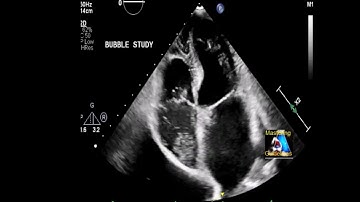

Beyond the Basics: A Modern Framework for High-Quality Bubble Studies